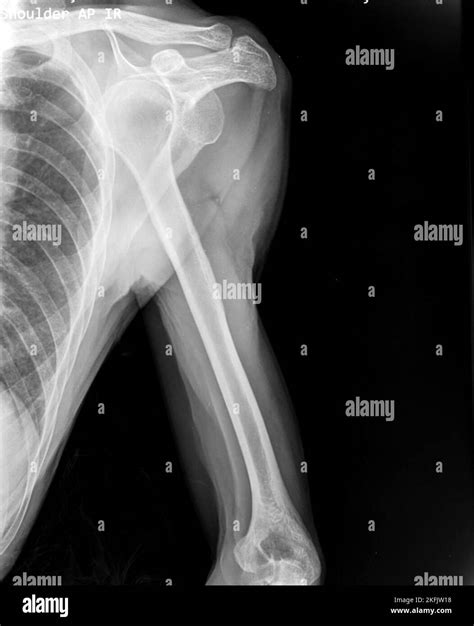

Typically, the technician will request at least two or three different views of the shoulder to ensure a comprehensive diagnosis:

• Anteroposterior (AP) View: Taken from the front, this view helps doctors see the general relationship between the humerus and the socket.

• Axillary View: This view captures the shoulder from underneath, which is crucial for identifying if the bone has moved forward or backward.

• Scapular Y View: This provides a lateral perspective, allowing the radiologist to see if the humeral head is centered in the socket of the scapula.